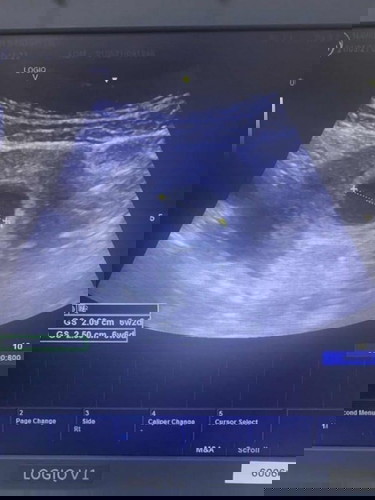

อายุครรภ์ไม่ตรงกับกับเครื่องซาวน์

ตอนนี้กังวลมากเลยค่ะ ถ้านับอายุครรภ์จากประจำเดือนจะ 8 w พอดี แต่เมื่อไปซาวน์กลับไม่พบตัวอ่อน คุณหมอแจ้งว่าเสี่ยงท้องลมถ้าไม่เจอตัวอ่อน แต่อายุครรภ์ตามเครื่องซาวน์แค่ 6w6d เราควรยึดอายุครรภ์จากตรงไหนค่ะ ใครเคยเจอกับประสบการณ์แบบนี้บ้างค่ะ รบกวนช่วยแชร์ความคิดเห็นหน่อยค่ะ #ปกติแม่ๆ ซาวน์เจอน้องกันตอนกี่สัปดาห์ค่ะ #ขอบคุณสำหรับคำตอบค่ะ